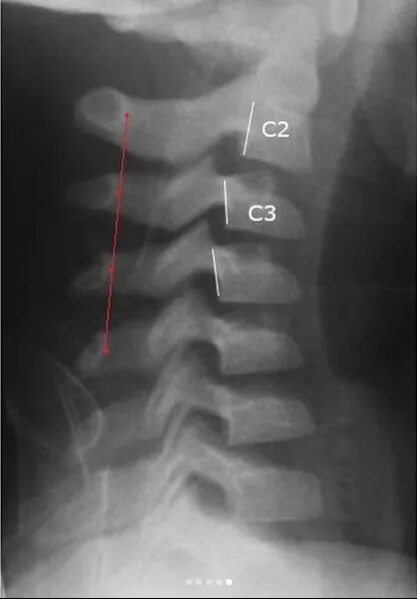

Нестабильность сегмента с3